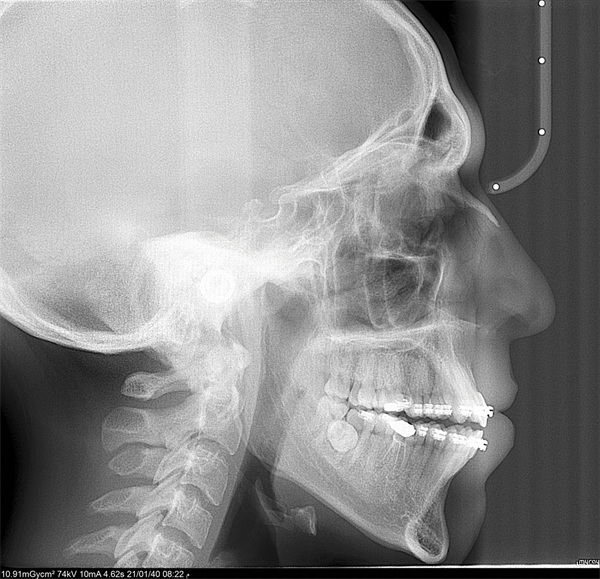

The cephalometric findings pointed clearly toward vertical maxillary excess. The asymmetric molar relationships, increased lower facial height, and posterior crossbite tendency all reinforced a picture that self-ligating brackets and wire changes were never going to resolve. The community’s response was equally clear: The ideal treatment is orthognathic surgery. The harder question was what to do when surgery is not a viable option (Figs. 1–10).

Fig. 1